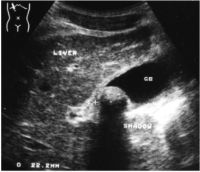

2- An acoustic shadow posterior to the echogenic focus (Picture 2).

The mobility of an intraluminal focus is a sign that is useful in equivocal cases (i.e., where a definite acoustic shadow is not demonstrated). It may be difficult to elicit a shadow behind small calculi (e.g., <5mm), depending on the ultrasound beam characteristics. The production of the shadow depends on the size of the calculus, the orientation of the calculus, the surface characteristics of the calculus (smooth vs. rough), and the beam geometry. The clear posterior shadow is produced by absorption of sound by calculi.

Picture2. Acoustic shadow.